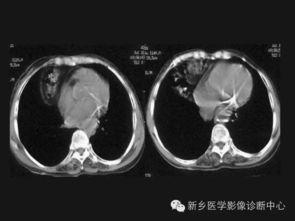

帕金森病是一种常见的神经系统退行性疾病,主要症状包括震颤、僵硬、运动迟缓和姿势平衡障碍。视频中,我们可以清晰地看到这些症状的表现。